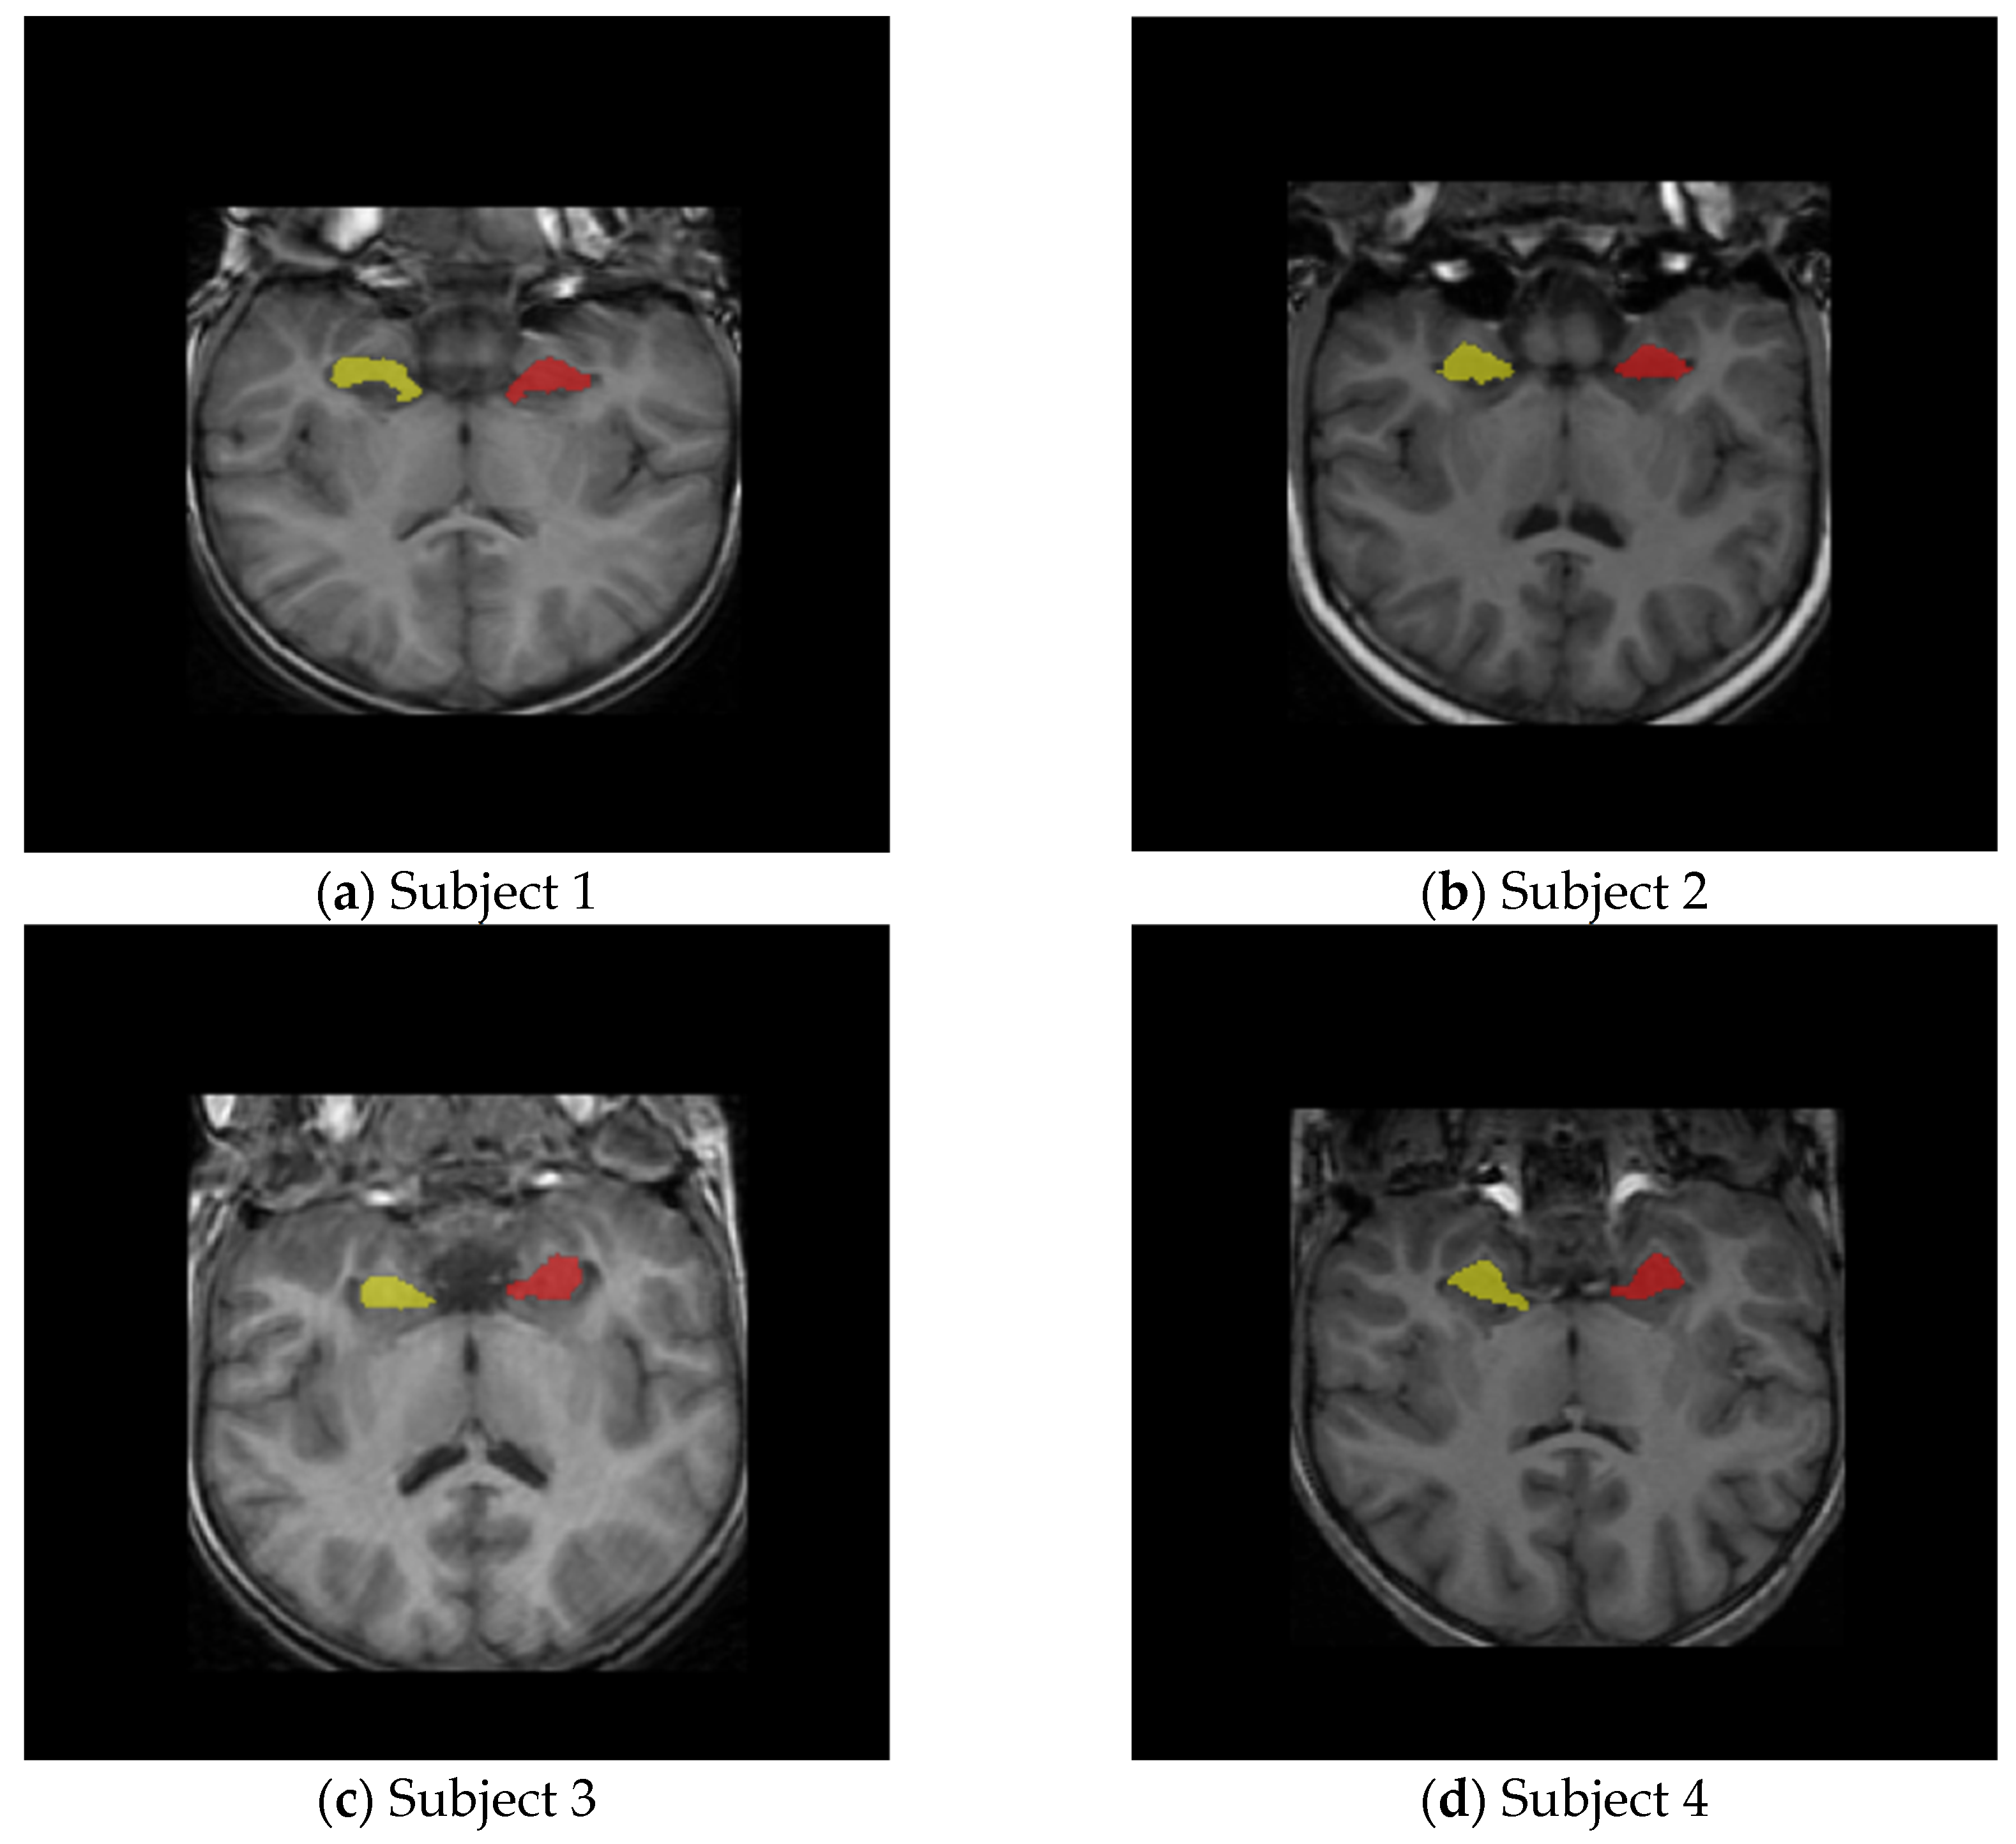

Overlay visualizations are performed using nibabel (Version 5.4.0) for NIfTI parsing and matplotlib (Version 3.10.5) for slice-by-slice rendering as shown in Figure 1.

Figure 1.

Hippocampus overlay masks on four subject samples.